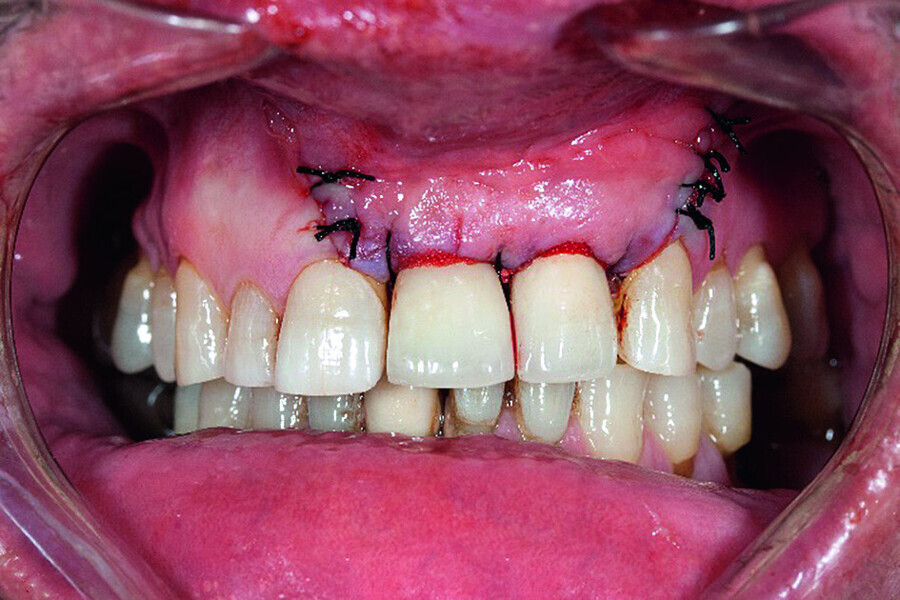

Peri-implantitis therapy